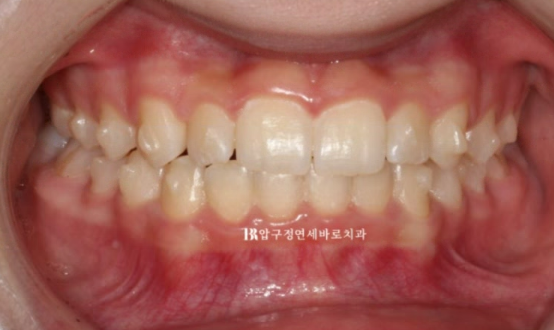

23.11

23년 4월부터 23년 11월까지 8개월 간 14개의 장치를 다 낀 후의 사진입니다.

덧니는 많이 개선이 되었으나 중심선이 맞지 않습니다.

여기서 다시 처음에 세웠던 치료 계획 시뮬레이션을 보면 중심선이 맞게 끝난다고 되어 있습니다.